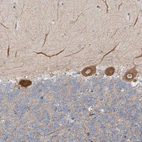

Immunohistochemical staining of human gallbladder shows strong granular positivity in cytoplasm in glandular cells.